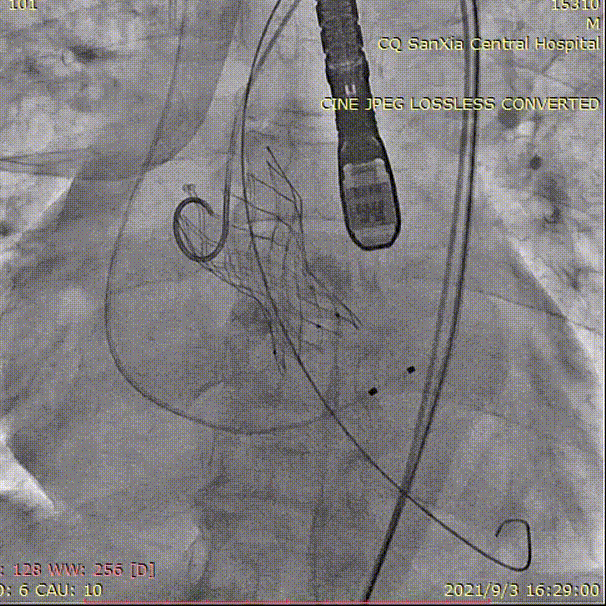

造影评估

吴中杰老师对这台手术进行了总结:本院这台手术过程复杂,但结果是令人满意的。该患者主动脉瓣极重度钙化,且延续广泛,瓣上限制区域重,伴有全心增大、心肌薄、EF值低,手术风险和难度极高。因此对瓣膜的大小、释放位置有较高的要求,否则发生重度瓣周漏的风险较高。

对于这个病例我们经过术前讨论,预估到了术中可能出现的风险,并做出了完善的应对措施,而且采用启明的VenusA—Plus瓣膜支架,具有可回收功能,也保障手术能达到最佳效果,总体来说通过术前完善的准备和术中流畅的配合,手术是非常成功的。